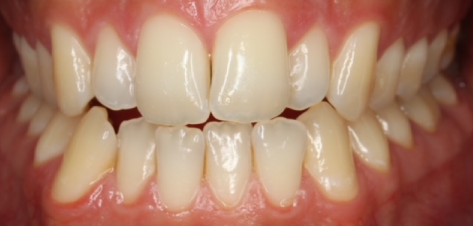

Blanqueamiento

Dra. Carmen Feito Bárcena

El paciente vino con una sonrisa con coloración más apagada y manchas. Tras el tratamiento con un blanqueamiento dental, se muestra una clara mejoría en luminosidad, con un aspecto homogéneo.